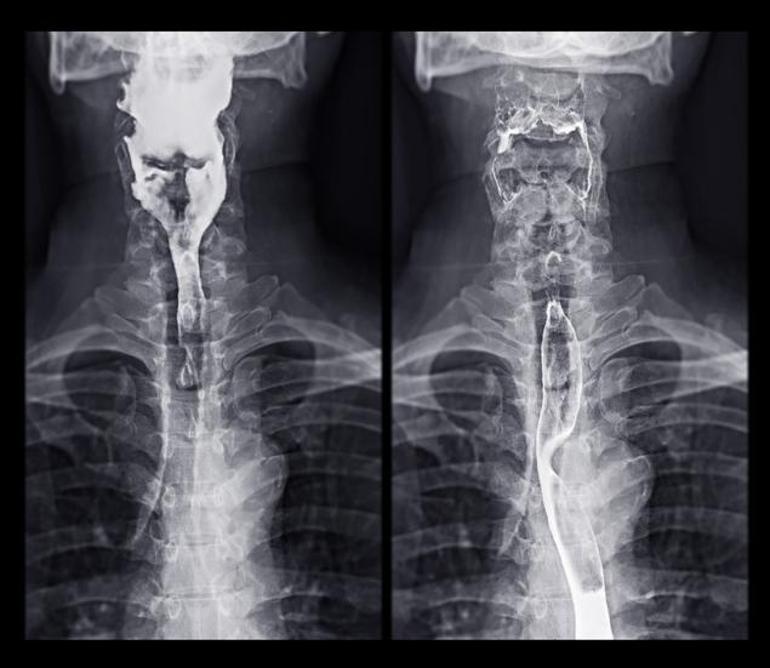

“Bu durum bende inatçı asit reflüsünün neden olduğu bir durum olan Barrett özofagusu gelişmesine yol açtı. Alışılmış bunu o vakitler hiç duymamıştım. Yılardır bu sorunu yaşıyordum, mide yanmasını ağır iş tempoma ve gerilime bağlıyordum, zira hayatım katiyen gerilimliydi. Çok gerilimli bir iş ve meskende iki küçük çocuğun yanı sıra, o yılın başlarında Londra’daki kiralık dairemden çıkmayı reddeden kiracılarım yüzünden uzun müddet hukuk gayreti verdim. Bu durum herkesin saçını başını yolması için kafiydi.”

Mide yanması şikayetiyle hastaneye gidip muhtemelen göğsünde bir kanserle çıkmanın çok acımaz bir latife üzere olduğunu söyleyen Sam üçüncü evre özofagus kanseriydi. Kanser ilerlemiş, büyümüş ve lenf düğümlerine yayılmıştı.

Kanserin midesine ya da bedeninin öbür bir yerine yayılmadığını denetim etmek için bir dizi tetkik daha yaptırdı. Sonunda, kemoterapi ve akabinde yemek borusunun birçoklarını çıkarmak için ameliyat oldu.

“Bana daima mide ekşimesinin kansere neden olabileceği söylendi zira mide ekşimesinin yemek borusuna verdiği daima hasar, orada bir tümörün büyümesini daha mümkün hale getiriyor. Mide yanması yemek borusu tümörlerinin hem belirtisi hem de nedenidir. Keşke bunu yıllar evvel bilseydim lakin tekrar de şanslıydım. Kanserim o sandviç sayesinde vaktinde yakalanmamış olsaydı, bu öyküyü anlatmak için burada olmayabilirdim.”